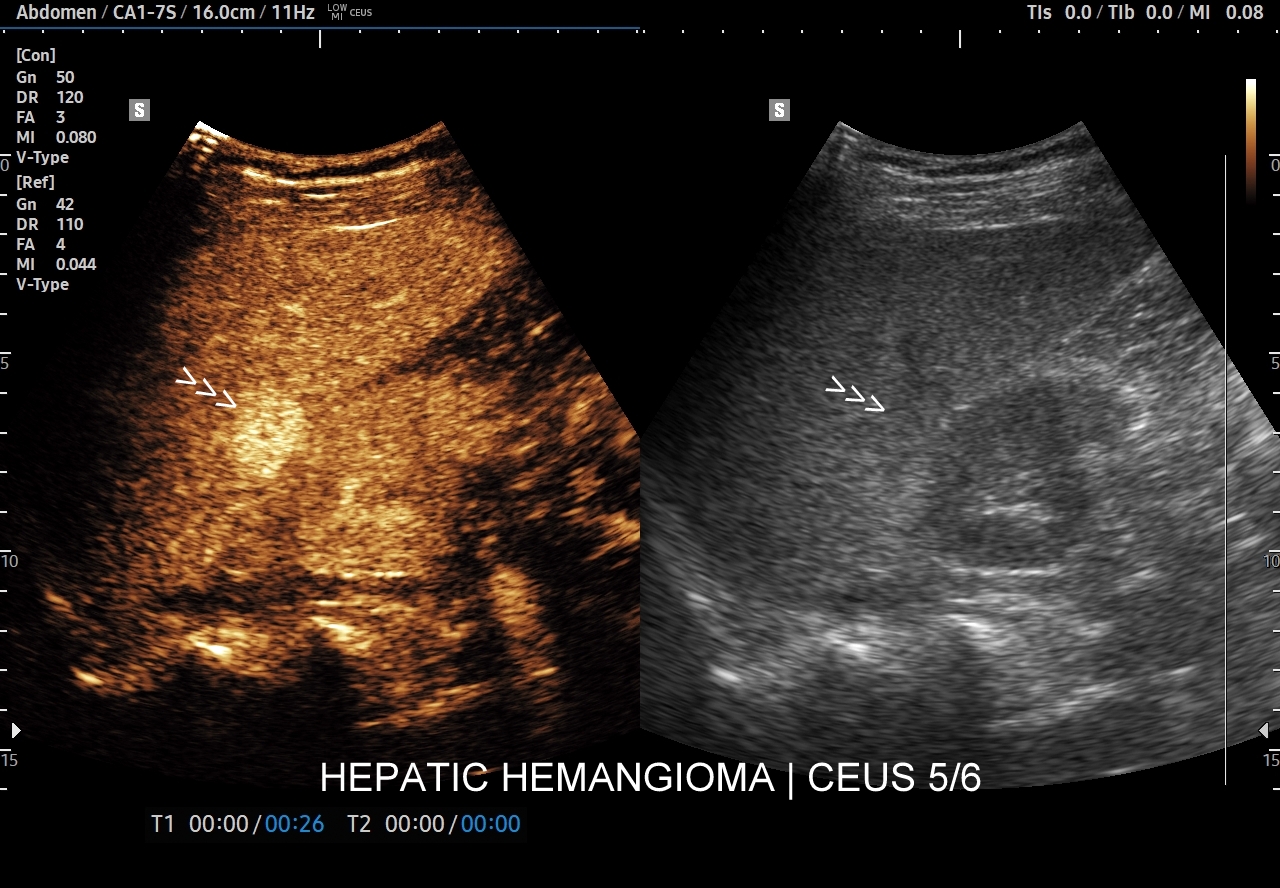

Najbardziej charakterystyczną cechą naczyniaka wątroby w badaniu CEUS jest jego wypełnianie w postaci guzkowej (ang. peripheral nodular enhancement) od obwodu ku centrum zmiany (ang. centripetal). Szybkość wypełniania bywa różnorodna, może być powolna lub szybka. W przypadku szybkiego wypełniania (tzw. flash-filling), w celu wykazania charakterystycznego centrypetalnego wypełniania niezbędna może być postprocessing’owa analiza poklatkowa zapisanego nagrania badania. W fazie późnej naczyniak wątroby pozostaje izowzmocniony lub hyperwzmocniony w stosunku do natywnego miąższu wątroby.

W przypadku dużych naczyniaków obszary, które uległy wykrzepianiu pozostają awaskularne przez wszystkie fazy badania CEUS, tj. nie wypełniają się kontrastem (nonenhancing). W przeciwieństwie do powyższego konstelacja, w której to w fazie wczesnej pojawia się wzmocnienie, a następnie w fazie wrotnej lub późnej ulega wypłukaniu (hypoenhancement) świadczy o cechach złośliwych diagnozowanej zmiany ogniskowej w wątrobie i wyklucza rozpoznanie naczyniaka.